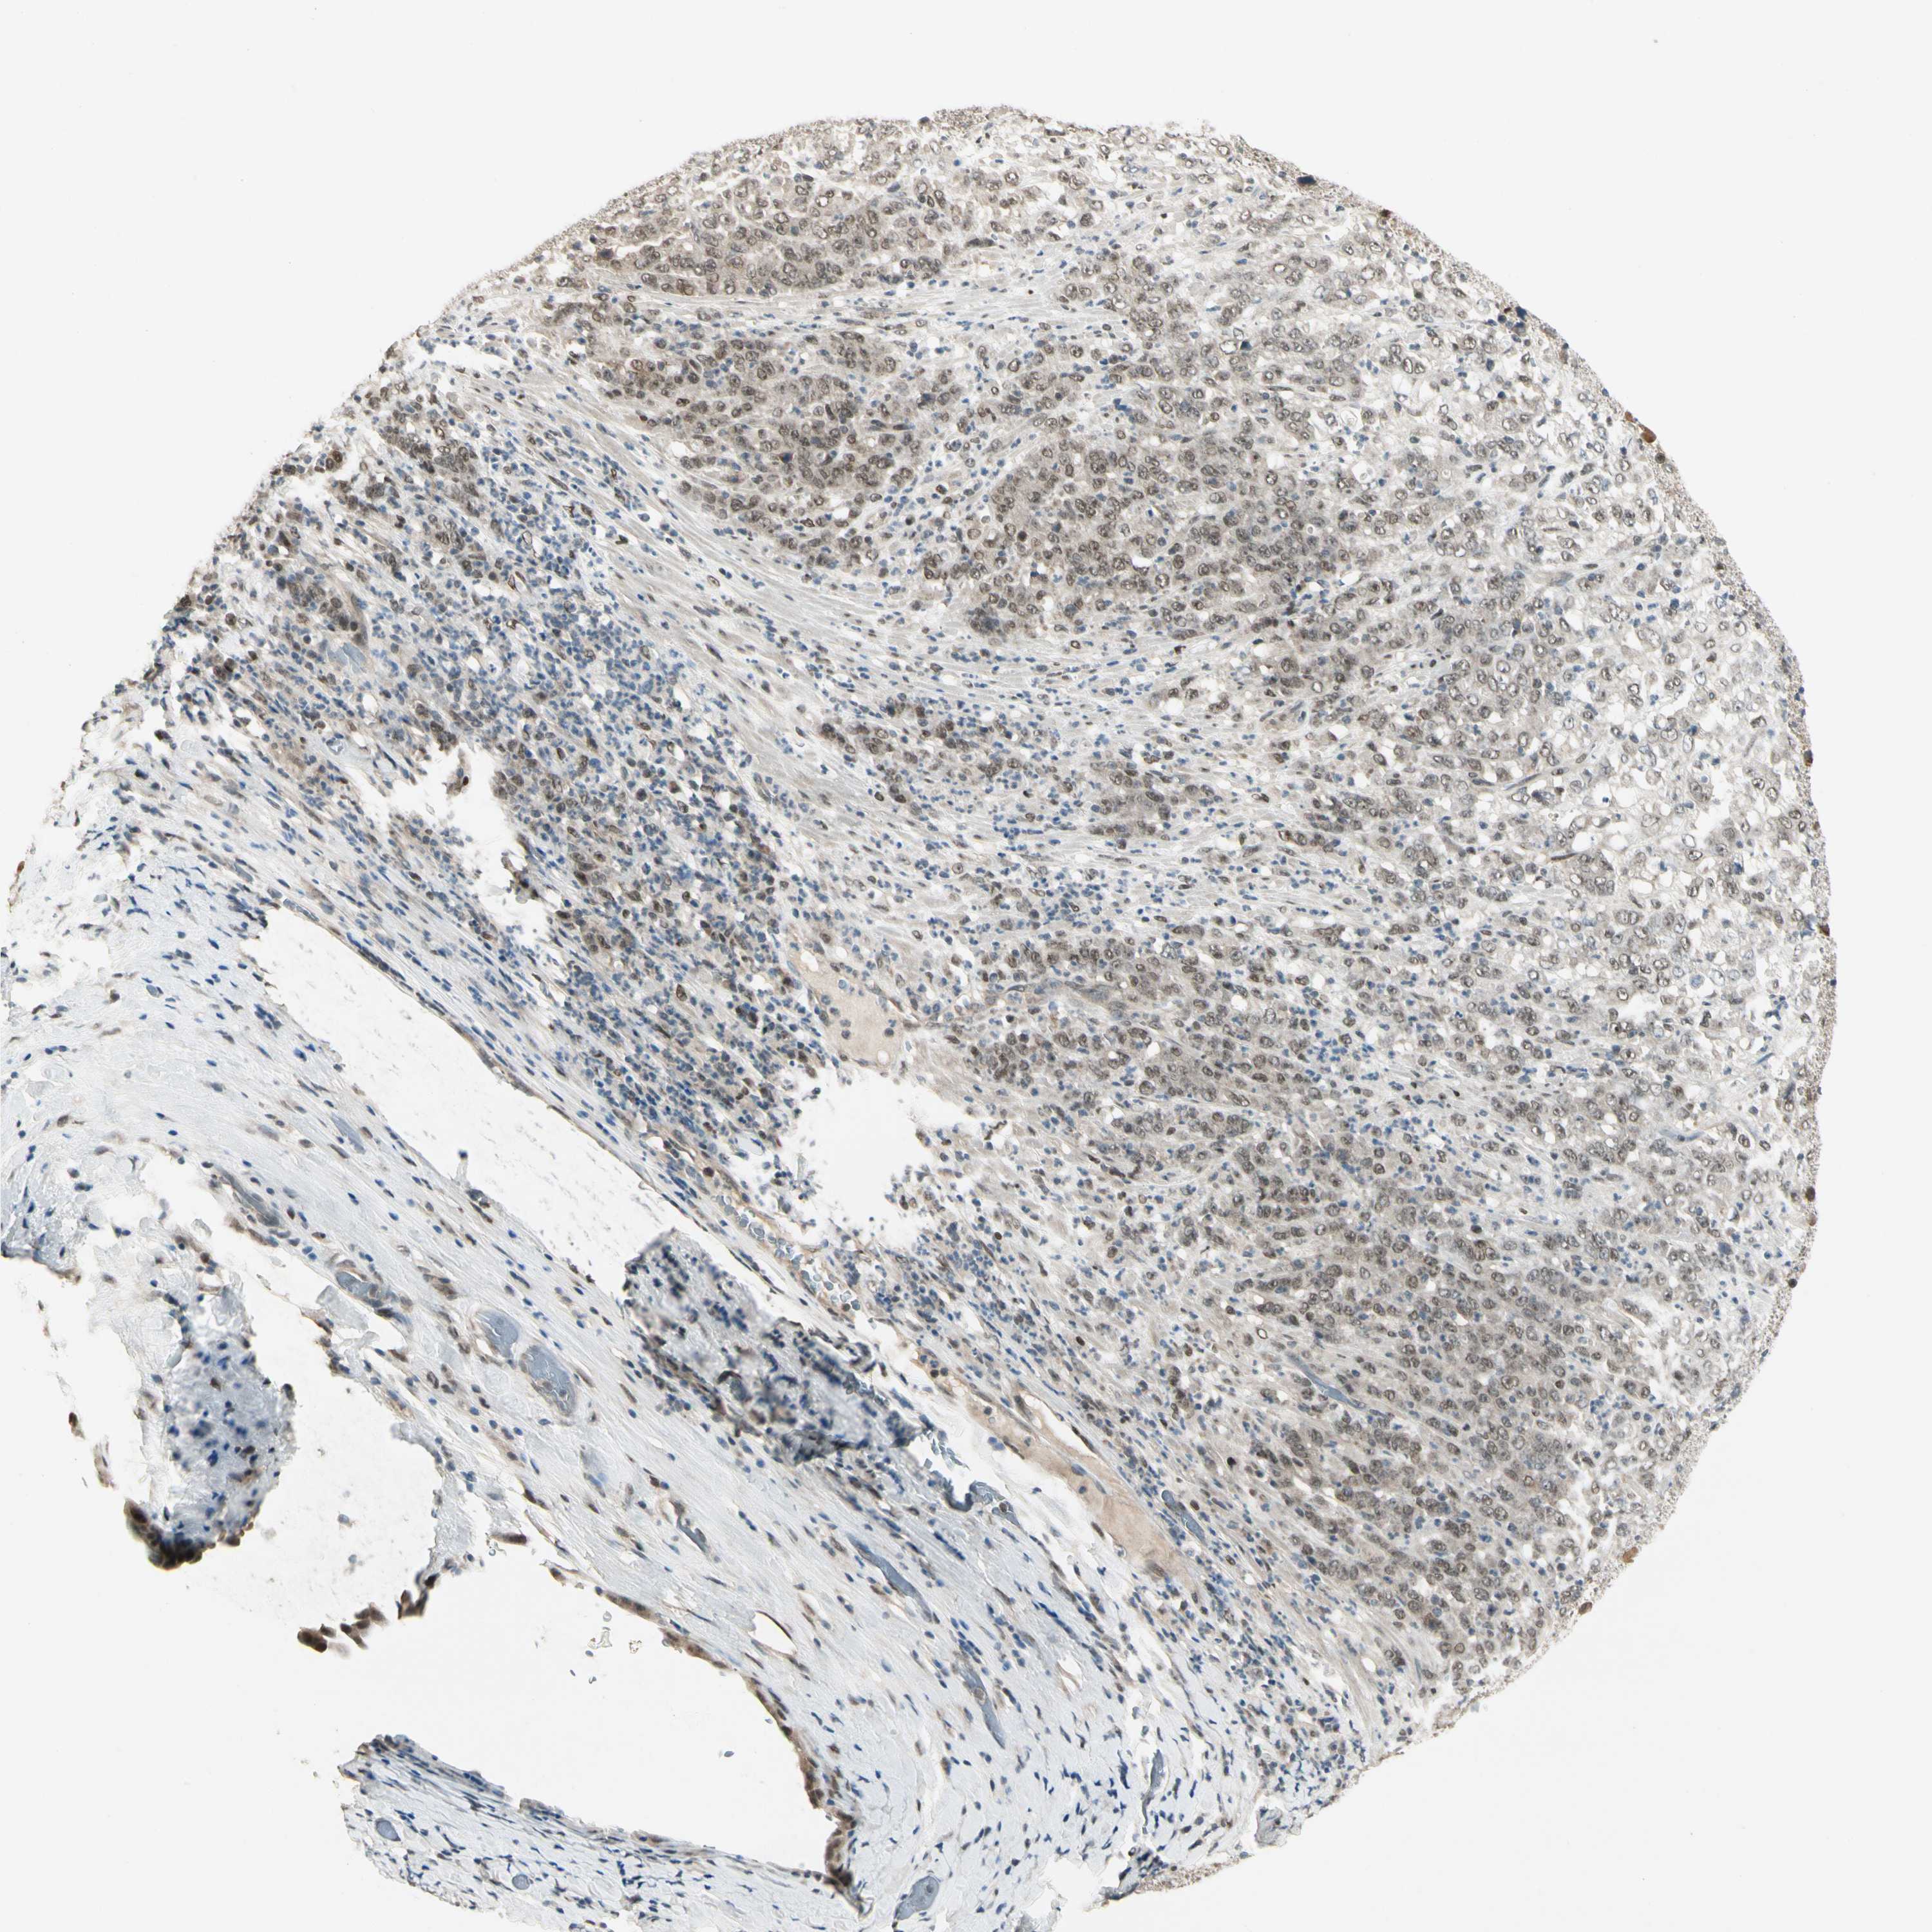

STOMACH CANCER - Protein expressioni

A mouse-over function shows sample information and annotation data. Click on an image to view it in a full screen mode. Samples can be filtered based on level of antibody staining by selecting one or several of the following categories: high, medium, low and not detected. The assay and annotation is described here.

Antibody stainingi

Antibody staining in the annotated cell types in the current human tissue is reported as not detected, low, medium, or high, based on conventional immunohistochemistry profiling in selected tissues. This score is based on the combination of the staining intensity and fraction of stained cells.

Each image is clickable and will lead to virtual microscopy that enables deeper exploration of all samples and also displays staining intensity scores, fraction scores and subcellular localization as well as patient and tissue information for each sample.

Antibody HPA007990

Staining

High

Medium

Low

Not detected

Intensity

Strong

Moderate

Weak

Negative

Quantity

>75%

75%-25%

<25%

None

Location

Nuclear

Cytoplasmic/membranous

Cytoplasmic/membranous,nuclear

Adenocarcinoma, NOS